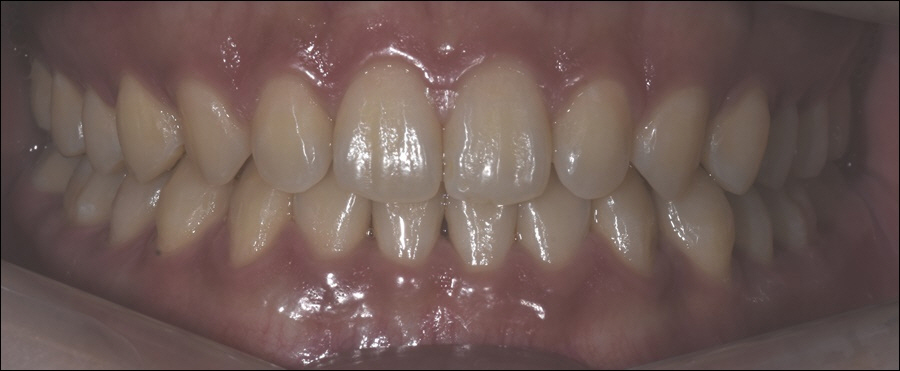

before->after